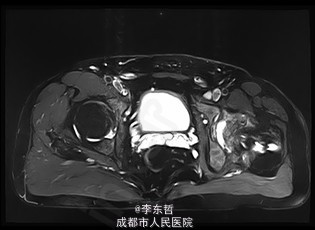

患者男,31岁,因“左股骨头股骨颈骨折切开复位内固定术后1+年”入院。患者1+年前因车祸致左股骨头、颈粉碎性骨折伴坐骨神经损伤于我院就诊,于我院行左股骨头股骨颈骨折切开复位空心钉+可吸收镙钉内固定术,术后恢复良好出院。术后8月后扶双拐活动。7月前患者无明显诱因出现左髋部疼痛,以负重时为重,后患者只能扶双拐活动。现患者为进一步治疗入我院。患病以来患者精神可,食欲可,睡眠可,大小便未见明显异常,体重无明显变化。

查体:T:36.2oC,P:80次/分,R:20次/分,BP:112/74mmHg。神志清楚,无病容,皮肤巩膜无黄染,全身浅表淋巴结未见肿大。颈静脉搏动、心界正常,心律齐,各瓣膜区未闻及杂音。胸廓未见异常,双肺叩诊呈清音,双肺呼吸音清,未闻及干湿啰音及胸膜摩擦音。腹部外形正常,全腹柔软,无压痛及反跳痛,腹部未触及包块,肝脏肋下未触及,脾脏肋下未触及,双肾未触及。双下肢无水肿。视:左髋外侧可见一约30cm手术瘢痕,其上可见一点状结痂,左腿较右腿短缩,左腿肌肉较右腿萎缩,步态异常。触:左髋部无压痛,左腿外侧感觉异常,以左膝外侧为重,左髋外侧叩击痛,左足背动脉搏动未扪及异常。动量:左下肢较右下肢短缩约3cm,左髋关节活动受限,其余各关节未见明显异常。

入院诊断:左股骨头股骨颈粉碎性骨折切开复位内固定术后坏死;积极完善术前检查及准备后行关节置换术。